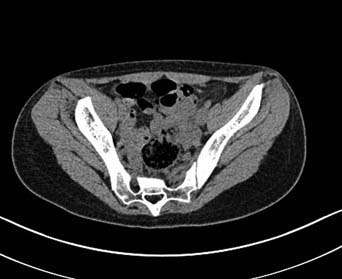

Здравствуйте.Помогите с диагнозом и тактикой лечения.

Больная 15 лет. Жалобы: на укорочение правой нижней конечности, хромоту. Анамнез: Со слов

болеет с детства, травму отрицает. Ранее за медицинской помощью не обращалась. Последние 2

года отмечает резкое укорочение конечности. Локально: При осмотре отмечается умеренное

искривление позвоночника во фронтальной плоскости, умеренная асимметрия лопаток и

надплечий. Скошенность таза. Отмечается укорочение правой нижней конечности на 3 см.

Движения в тазобедренном и коленном суставах в полном объеме. Нейрососудистых нарушений в

периферических отделах нет.